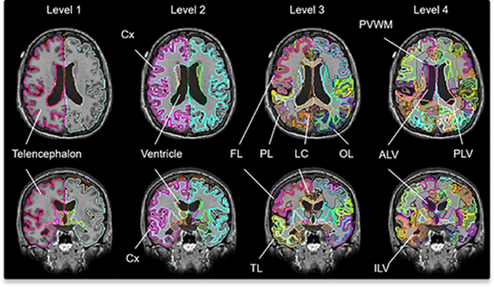

※解析で使用している画像の一部です。検診結果の報告書の表示と異なります。